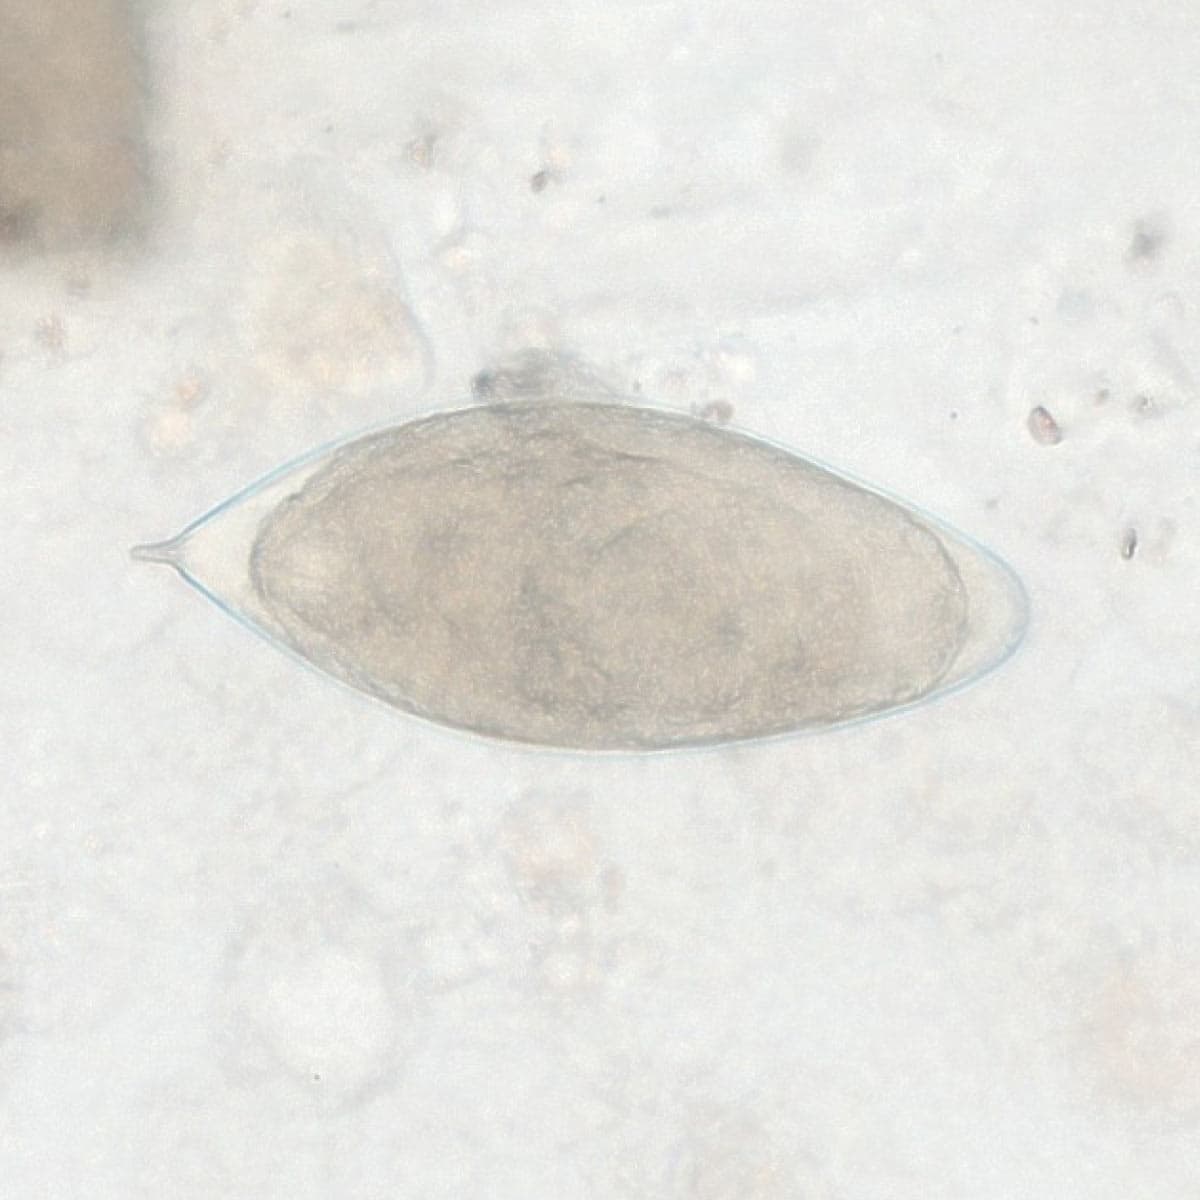

Automatic detection of rare species

Built on worldwide parasite-positive specimens, ParaScout AI identifies a vast number of parasite species, including those that are clinically rare or challenging to find.